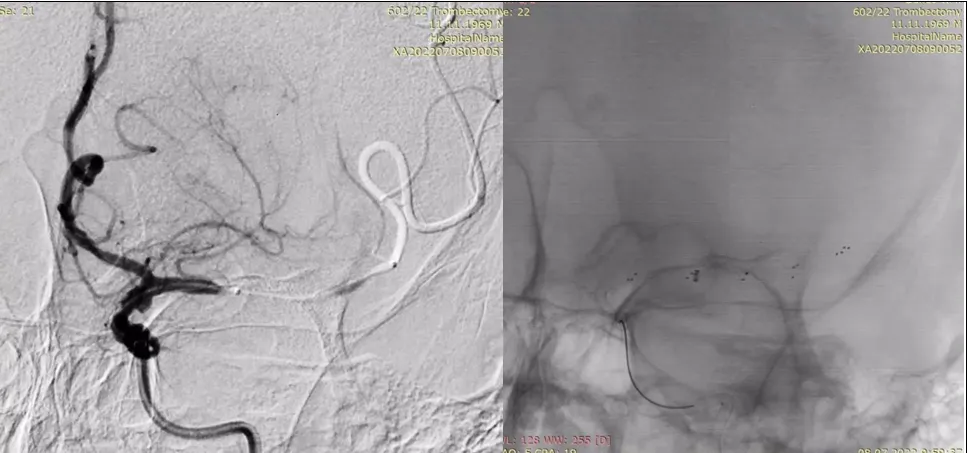

Для анестезіологічного забезпечення механічної тромбектомії застосовували седацію зі збереженням свідомості із забезпеченням кисневої підтримки через маску – 4 л/хв. АТ при ініціальному вимірюванні дорівнював 183/95 мм рт.ст. та не знижувався до моменту реперфузії басейну СМА. Час від початку захворювання до пункції стегнової артерії в ендоваскулярній операційній – 1255 хвилин. Оскільки дані МСКТ – ангіографії вказували на тандемну оклюзію (устя лівої ВСА та сегменту М1 лівої СМА) та демонстрували хорошу колатеральну компенсацію басейну лівої СМА, трансфеморальним доступом операційним провідниковим катетером відразу була проведена катетеризація лівої загальної сонної артерії без етапу діагностичної ангіографії. Цифрова субтракційна ангіографія дозволила з’ясувати місце відходження лівої ВСА від загальної сонної артерії та за допомогою балонного катетера для черезшкірної ангіопластики (percutaneous transluminal angioplasty balloon catheter) сформувати канал на рівні тромбованої атеросклеротичної бляшки ВСА (рис. 4) з метою проведення за межі оклюзії у дистальному напрямку операційного провідникового катетера.

Рисунок 4. Цифрова субтракційна ангіографія, лівий каротидний басейн, ліва косо- фронтальна проекція. Місце відходження лівої ВСА від загальної сонної артерії (червона стрілка). Наповнення балонного катетера на рівні тромбованої атеросклеротичної бляшки (балон позначено жовтою стрілкою).

Далі ангіографія через аспіраційний катетер підтвердила тромбоз СМА на рівні сегменту М1 після чого за місце оклюзії СМА був проведений мікрокатетер та через нього виконано дистальне контрастування, необхідне для уточнення місця розкриття стент-ретривера (рис. 5)

Рисунок 5. Цифрова субтракційна ангіографія, лівий каротидний басейн, передньо-задня проекція. Червоними стрілками позначено розташування тромбів у сегментах М1та М2 лівої СМА. Жовтою стрілкою позначено дистальний маркер мікрокатетера, що був проведений за

місце оклюзії СМА та виконана суперселективна ангіографія.

Після розкриття стент-ретривера на рівні тромбозу СМА кінчик аспіраційного катетера при постійній аспірації за допомогою помпи провели безпосередньо до місця оклюзії та виконали тромбектомію технікою SAVE (stent retriever-assisted vacuum-locked extraction) (рис. 6).

Рисунок 6. Цифрова субтракційна ангіографія, лівий каротидний басейн, передньо-задня проекція. Визначення місця розкриття стент-ретривера по проксимальному та дистальному маркерам на мікрокатетері (позначені червоними стрілками). Стент-ретривер на рівні тромбу (позначений жовтими стрілками) та маркер аспіраційного катетера на рівні проксимальної частини тромбу (синя стрілка).

Після успішної реперфузії (eTICI 2c) басейну лівої СМА з першого пасу (рис. 7) одразу проведена корекція АТ до рівня 120/70 мм рт.ст, після чого виконана ангіопластика та стентування устя лівої ВСА (рис. 8). За 25 хвилин до імплантації стента внутрішньовенно болюсно було введено 750 мг ацетилсаліцилату лізину (ацелізину). Час від пункції стегнової артерії до реперфузії басейну лівої СМА – 55 хвилин.

Рисунок 7. Цифрова субтракційна ангіографія, лівий каротидний басейн, передньо-задня та

бокова проекції демонструють майже повну реперфузію басейну лівої СМА (eTICI 2c).